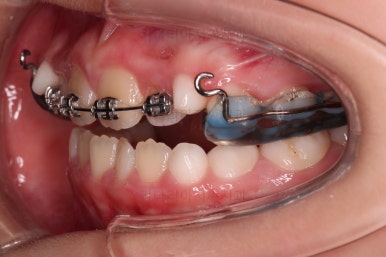

입 안에는 이런 장치가 들어가요.

착탈식은 아니고 부착형입니다.

앞니를 일부러 붕 띄워주며 위턱의 가로폭을 확장시켜주는 악궁확장장치도 부착이 되었어요.

어떻게 식사를 하냐며 걱정하시는 보호자분들이 계시지만 씹는 면을 편평하게 아랫니와 맞춰주었기 때문에 기존의 부정교합인 상태보다 오히려 식사가 잘 될 수 있으니 염려 안하셔도 됩니다.

위턱뼈가 가로로 넓어지니 앞니 사이에도 공간이 많이 생겼네요.

부분적으로 교정장치를 부착해서 당사자가 제일 고치고 싶어햇던 앞니 부분을 가지런하게 하기 시작했어요.

위턱뼈가 앞으로도 점점 나와서 처음 보다는 반대교합 경향이 개선되고 있는게 보이네요.

앞니도 굉장히 가지런해졌고요.